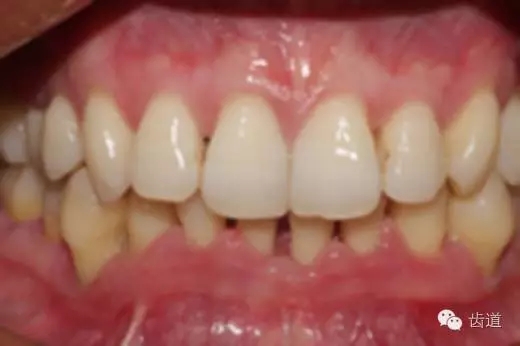

2、牙齦

5.webp.jpg

(顏色、形狀、質(zhì)地、退縮、BOP、PD、附著齦)

6.webp.jpg

7.webp.jpg

8.webp.jpg

9.webp.jpg